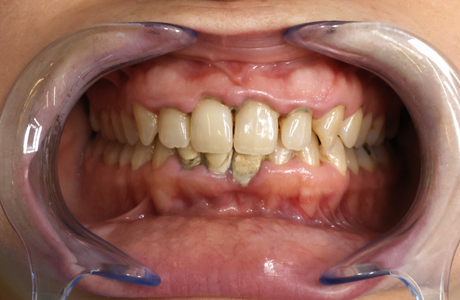

La gingivite est le premier stade de la maladie parodontale. La jonction gencive-dent est colonisée par des bactéries qui déclenchent une inflammation de la gencive. Rouge, gonflée et douloureuse, la gencive se décolle de la dent et le tartre s’accumule sous la gencive. A un stade avancé et en l’absence de traitement, la gingivite évolue en parodontite.

LA PARODONTITE

Au stade de la parodontite, la destruction porte alors sur l’os de la mâchoire et les ligaments de soutien qui ancrent les dents (ligament alvéolo dentaire). Des poches parodontales se forment et les bactéries s’y accumulent, avec plus ou moins de pus. A terme, le déchaussement de la dent peut amener la perte de celle-ci, accompagnée parfois d’une collection purulente très douloureuse.